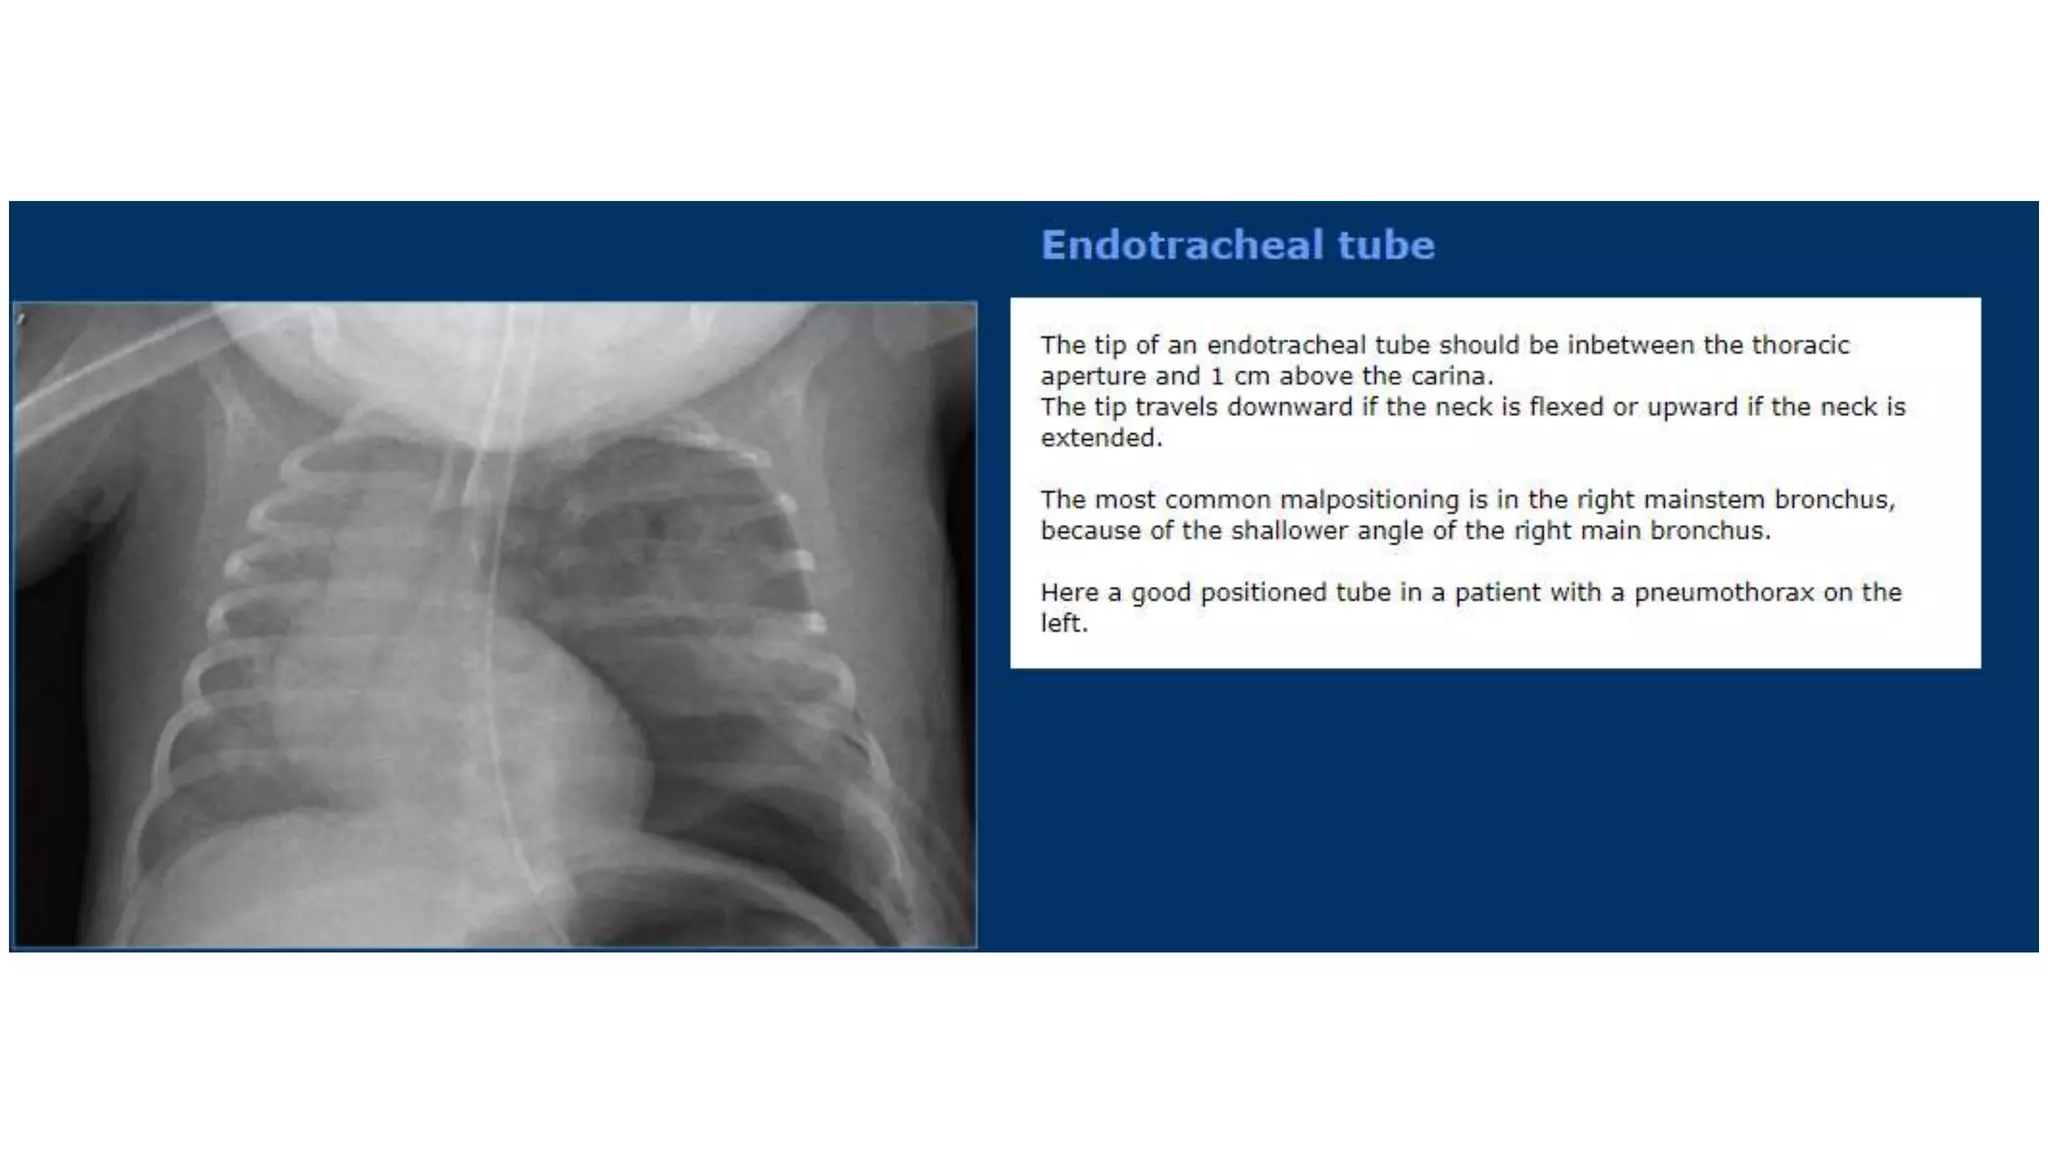

This document provides an overview of neonatal chest x-rays, including when they should and should not be performed, what a normal x-ray looks like, common positions of tubes and catheters, and common causes of respiratory distress in neonates. It discusses the appearance of a normal chest x-ray as well as conditions like respiratory distress syndrome, transient tachypnea of the newborn, meconium aspiration syndrome, and pneumonia. Surgical conditions like diaphragmatic hernia and esophageal atresia are also reviewed.